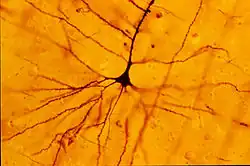

Cellule de Betz

Les cellules de Betz sont de grands neurones moteurs à noyau de forme pyramidale, d'où leur appellation de cellules pyramidales de Betz.

Elles se situent généralement dans la couche V du cortex moteur primaire (aire 4 de Brodmann).